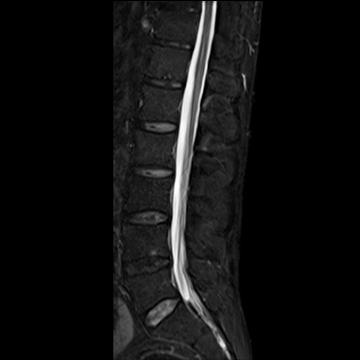

全脊椎

T1 TSE, 448 matrix

T2 STIR, 384 matrix,